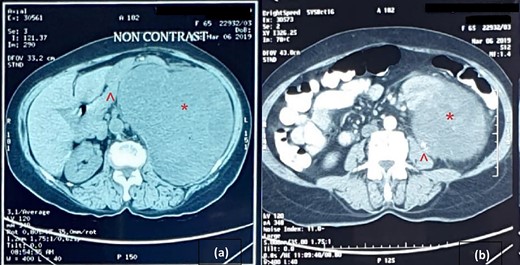

An abdominal ultrasound (US) revealed a 12 × 12 cm solid mass from the left suprarenal area (Fig. 1). Contrasted computed tomography (CT) revealed a 17.5 × 11.5 cm enhancing lesion in the left suprarenal region, completely replacing the left adrenal gland. The left kidney was inferiorly displaced, and coarse calcification was seen at the lesion’s periphery without lymph node enlargement. The contralateral adrenal gland, retroperitoneal and peritoneal structures were normal (Figs 2 and 3). Screening for primary carcinomas presenting as adrenal deposits utilizing clinical examination, pan endoscopy and contrasted CT were all negative. At this point, our working diagnosis was non-secreting left pheochromocytoma, and elective laparoscopic left adrenalectomy was planned.

Cross-sectional image of computer tomogram; (a) non-contrasted image and (b) contrasted image; the red asterisk mark in (a, b) shows the tumour, the red arrowhead in (a) shows anteriorly displaced pancreas and the red arrowhead in (b) shows the clear distinction of tumour from the left psoas.